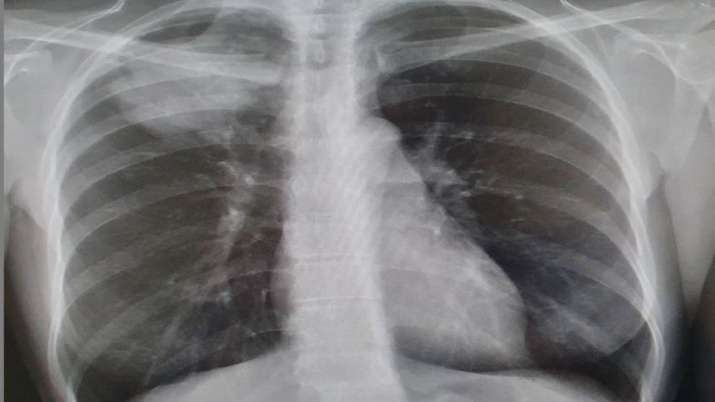

Using high-energy X-rays, scientists have found how Covid-19 damages even the smallest blood vessels in human lungs. Scientists from University College London and the European Synchrotron Research Facility (ESRF) used a new revolutionary imaging technology called Hierarchical Phase-Contrast Tomography (HiP-CT), to scan donated human organs, including lungs from a Covid-19 donor.

Using HiP-CT, the research team saw how severe Covid-19 infection 'shunts' blood between the two separate systems -- the capillaries which oxygenate the blood and those which feed the lung tissue itself. Such cross-linking stops the patient's blood from being properly oxygenated, which was previously hypothesised but not proven, said the team in the paper published in the journal Nature Methods.

The HiP-CT technique provides the brightest source of X-rays in the world at 100 billion times brighter than a hospital X-ray.

Due to this intense brilliance, researchers can view blood vessels five microns in diametre (a tenth of the diametre of a hair) in an intact human lung, whereas a clinical CT scan only resolves blood vessels that are about 100 times larger, around 1mm in diametre.